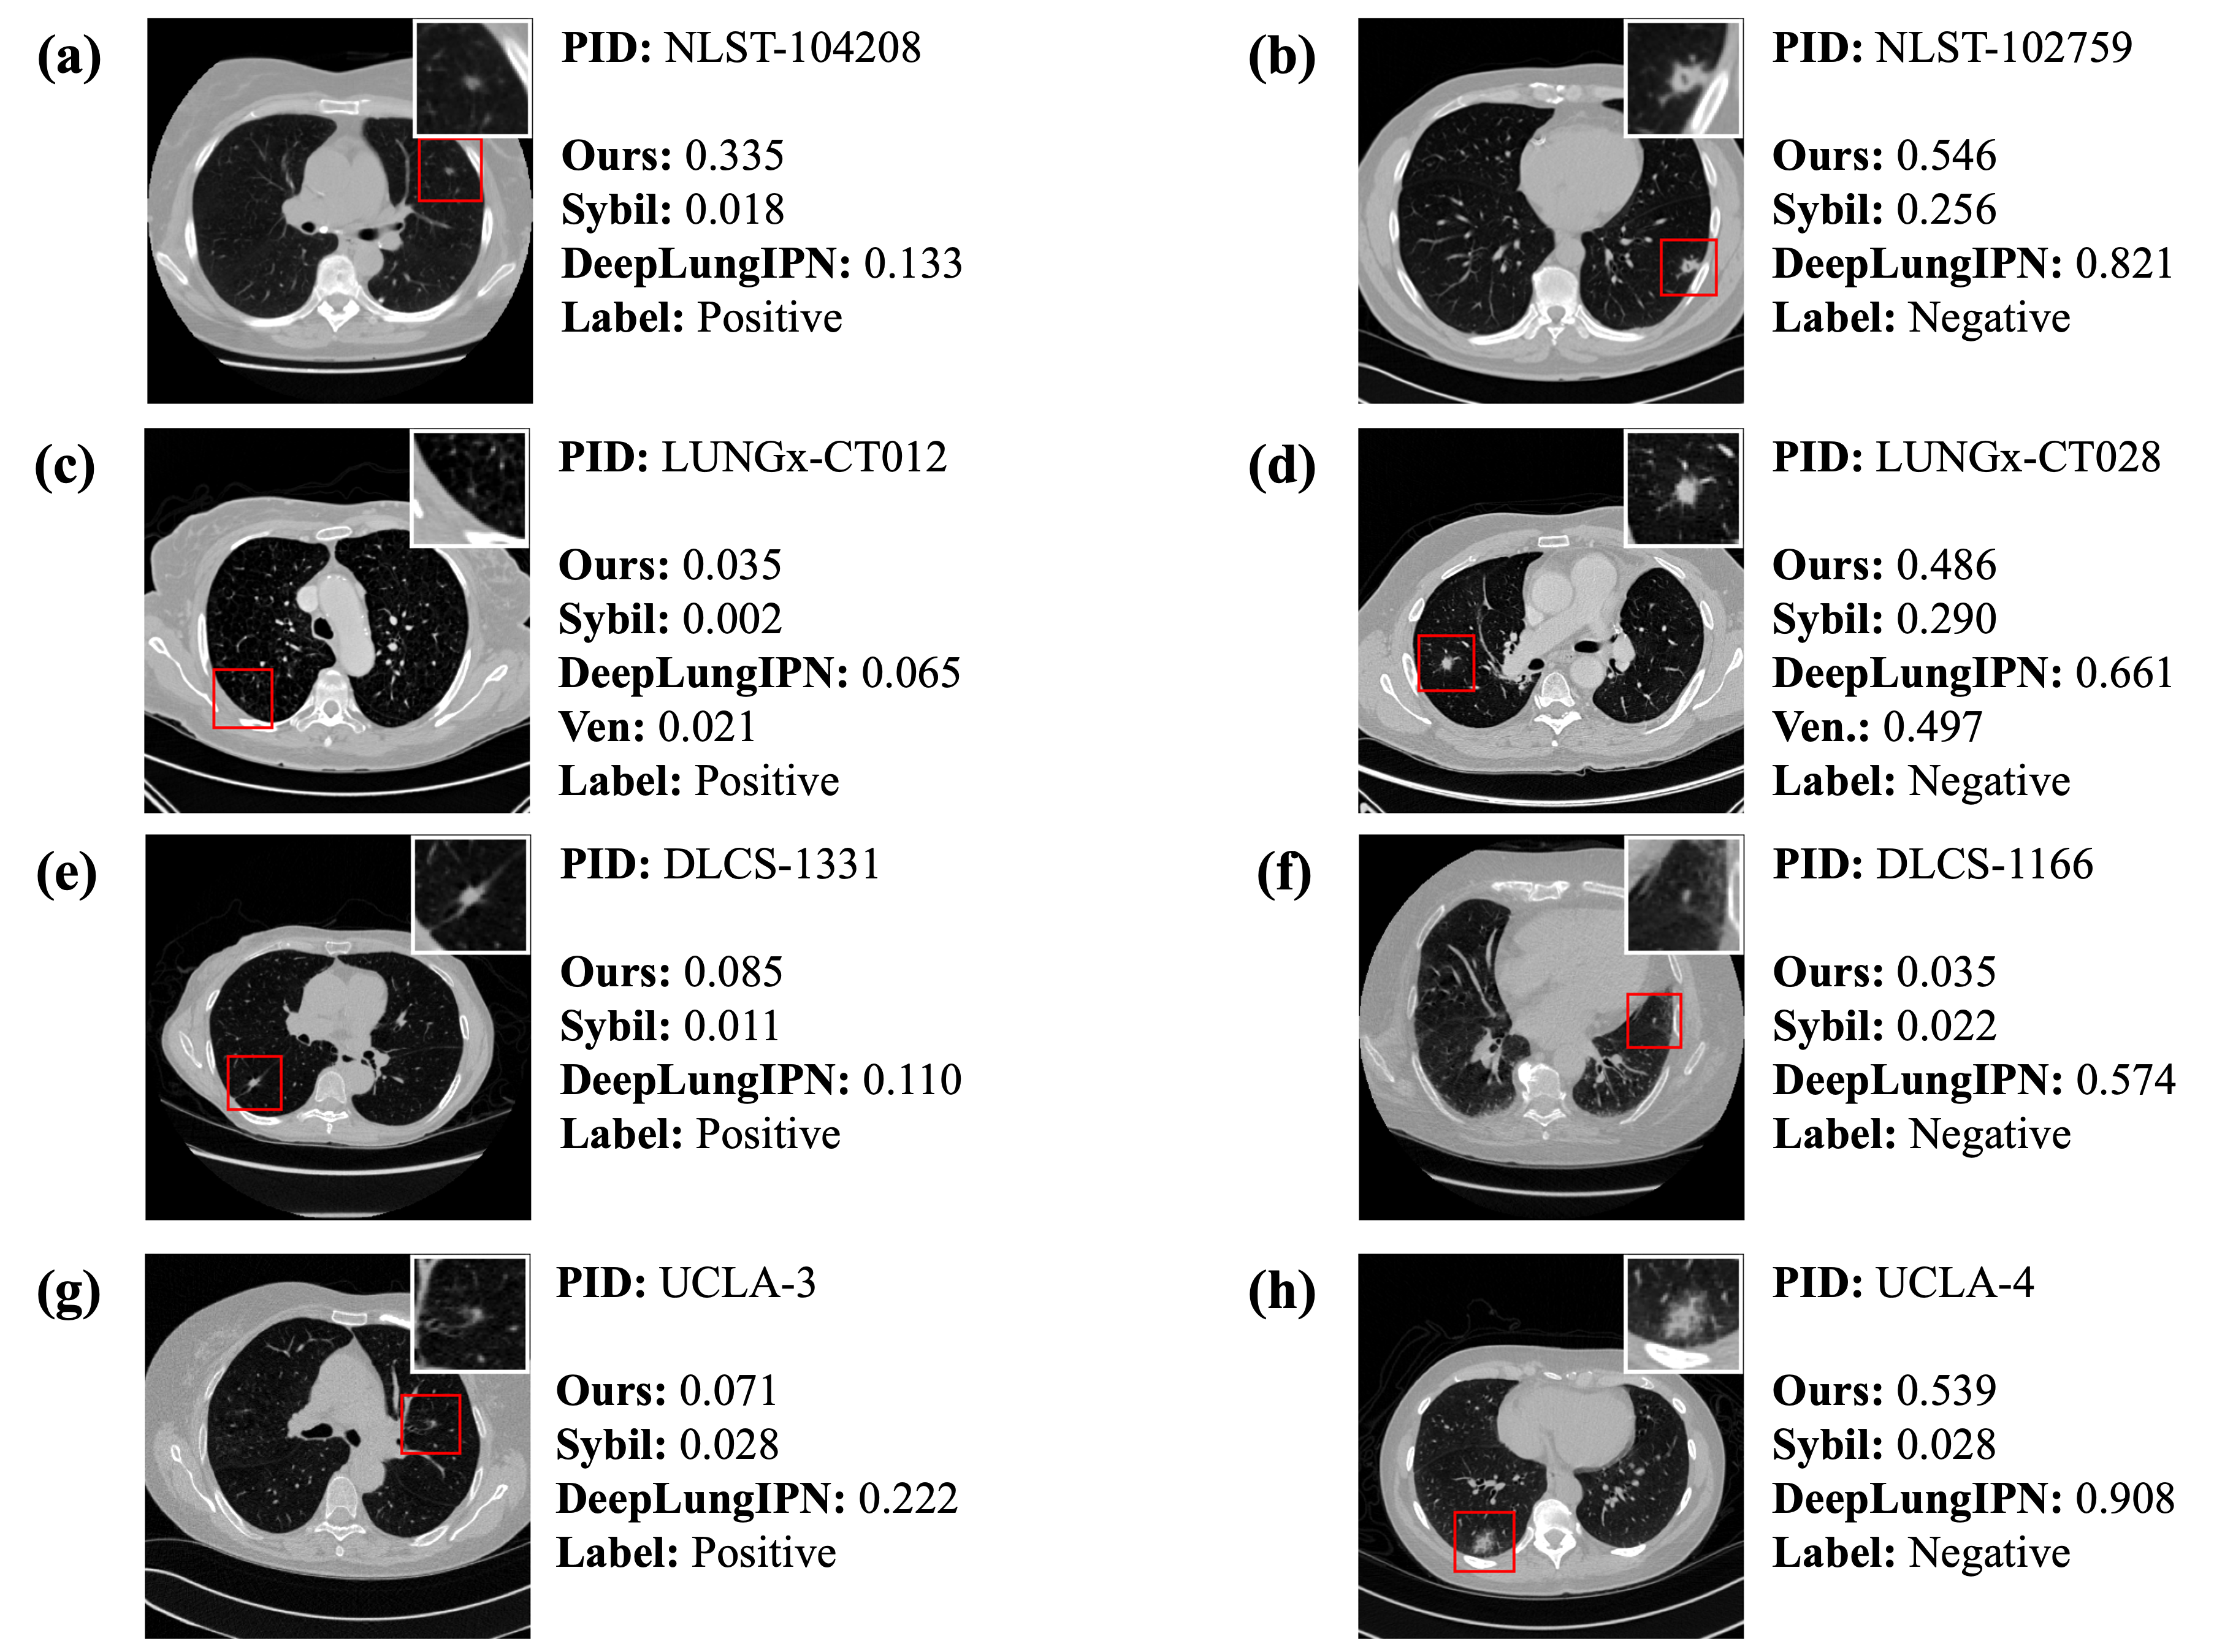

4.4 Error Analysis

In Fig. 3, we present a CT scan from a lung cancer patient and a non-lung cancer patient for each dataset. More examples are shown in Fig. A1. It is important to note that both Sybil and DeepLungIPN use only the CT scan as input, whereas our model and that of Venkadesh et al. incorporate both the CT scan and the nodule location as inputs. Although the pipeline in DeepLungIPN involves a nodule detection step, the detected nodules may not correspond to the annotated nodules shown in the figure.

In Fig. 3a and c, all models fail to identify the patient as high-risk even though they are diagnosed with lung cancer within a year. In Fig. 3a, the nodule crop shows a poorly marginated, pure ground glass nodule with an irregular margin. The malignant nodule in Fig. 3c is spiculated with a complex shape, septal stretching, and vascular convergence. Our model outputs relatively higher risk scores of 0.306 and 0.443, in contrast to the extremely low scores given by other models. Fig. 3e illustrates a challenging and uncommon case where the nodule is within the right main stem bronchus. All models assign a relatively lower score while the nodule is malignant. In Fig. 3g, a poorly marginated pure ground glass nodule is presented. Among the models, only DeepLungIPN successfully assigns a high risk score to this malignant case, while the others fail.

Fig. 3b shows a non-cancerous case with a lobulated and serrated nodule exhibiting complex shape and pleural retraction. While DeepLungIPN correctly identifies the case as low risk, our model assigns a high risk score of 0.821. In contrast, Fig. 3d and h illustrate two negative cases where DeepLungIPN assigns unusually high risk scores, whereas our model and others provide more conservative estimates. This discrepancy may stem from DeepLungIPN’s miscalibration, leading to overconfident predictions. Additionally, visual inspection revealed that DeepLungIPN sometimes detects non-nodule regions, which may contribute to inflated risk scores. In Fig. 3f, although the biopsy confirmed a benign finding, the nodule appears highly suspicious due to its large size, irregular shape, and spiculated margins. All models, including ours, assign high risk scores to this case. Radiologists also classified it as Lung Imaging Reporting and Data System (Lung-RADS) category 4X, indicating a high suspicion of malignancy with additional concerning imaging features [40].

Fig. A1c, e, and g depict nodules diagnosed as lung cancer, but our model underestimates the risk. Although these nodules are relatively small, they exhibit irregular shapes (c), spiculated margins (e), mixed densities (g), and pleural attachment (c, e, g). Interestingly, all other models also predict low scores for these nodules. In Fig. A1a, a lobulated, solid, well-marginated nodule is shown with a few suspicious features. It is reasonable that our model predicts a 33% likelihood of malignancy, but all other models assign extremely low scores to this cancer patient.

In Fig. A1b, the nodule is solid with spiculated and lobulated margins and an irregular shape. Concerning characteristics include cyst-like spaces and pleural retraction. In Fig. A1d, the nodule appears to be solid with spiculated margins, septal stretching, and vascular convergence. In Fig. A1h, a large, part-solid nodule with poorly defined margins is observed. Given these suspicious features, most models assign relatively higher risk scores, despite the patient not being diagnosed with lung cancer. However, in Fig. A1h, Sybil accurately identifies it as having a lower score. In contrast, Fig. A1f shows a tiny nodule with no apparent suspicious features, but DeepLungIPN assigns a comparatively higher risk. We found that the nodules detected by DeepLungIPN appear to be fibrosis and vessels.